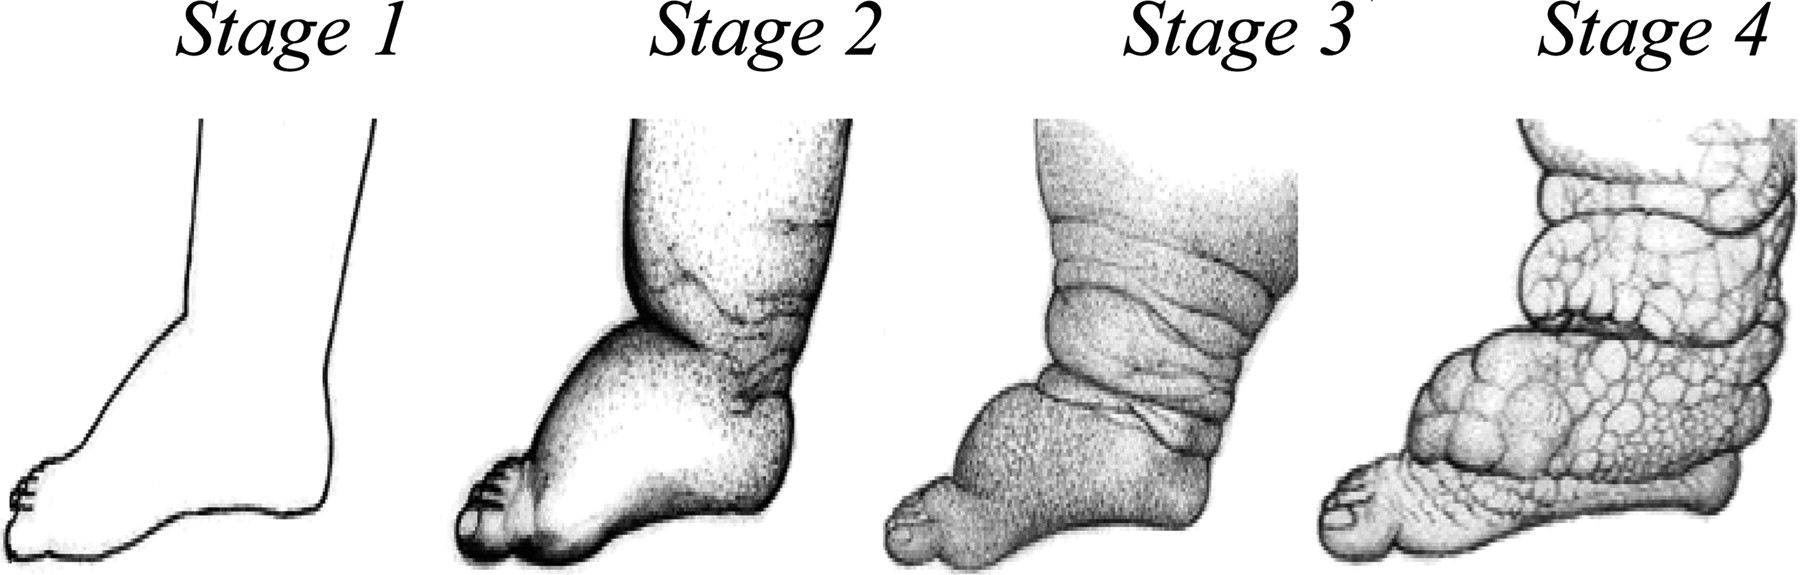

甚至有学者,详细追踪了丝虫病的发展的整个过程,从淋巴管炎、淋巴结炎到肢体、阴囊的逐步肿胀。

丝虫病发病各期表现

班氏吴策线虫和马来布鲁线虫引起的丝虫病,也被称为象皮病或象皮肿。

这是因为此2种丝虫,可寄生在人的腿部、阴囊、臂部等皮肤的皮下组织、淋巴系统、腹腔或胸腔内,然后分泌因子刺激皮肤增厚,并堵塞淋巴管,导致淋巴肿大,最终形成厚如大象皮一样的组织。

实际上只有丝虫寄生在淋巴管,才能导致象皮病。